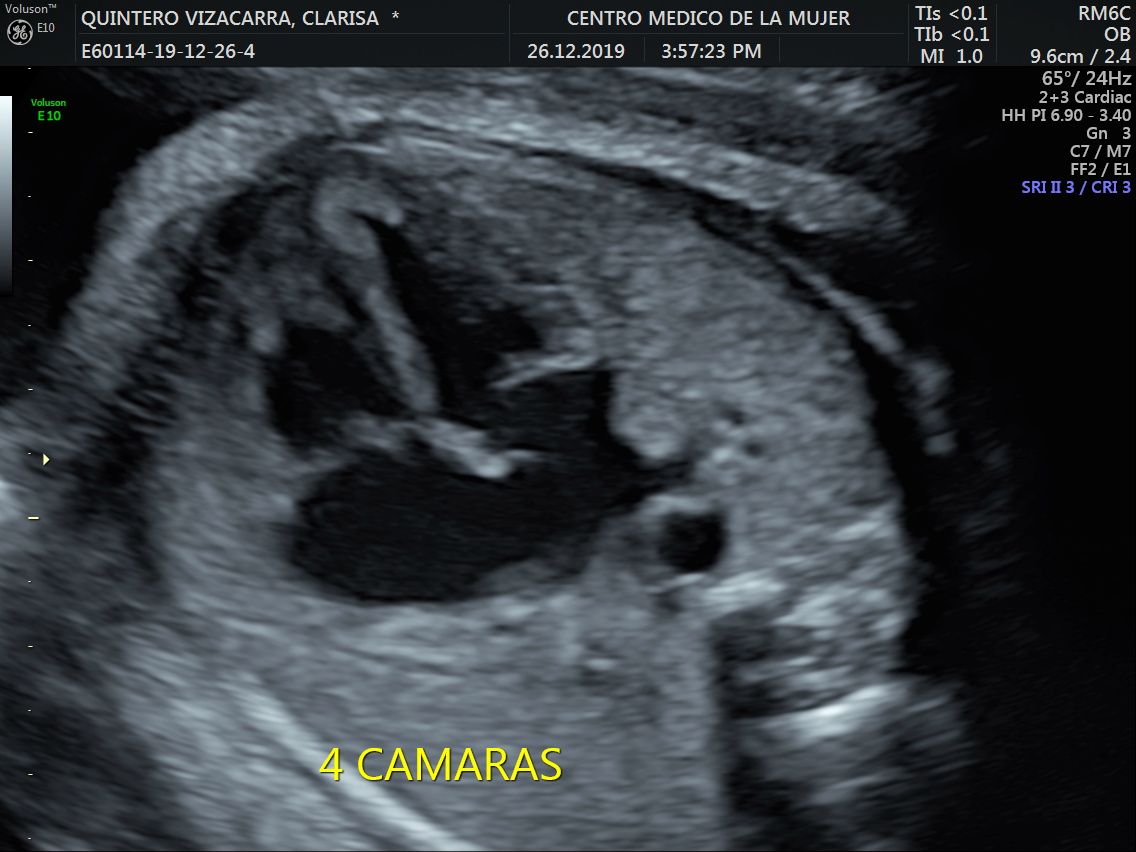

Fotos y videos

ECO Anatómico

Consiste en la evaluación especifica de cada organo y sistema del bebé con medidas detalladas de cada parte para evaluar su crecimiento proporcional.